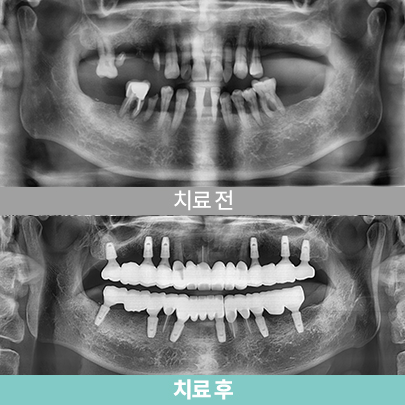

- 40대 남성, 치료 후 3개월

- 심미보철

- 심미보철

- 상·하악 풀마우스 임플란트

- 40대 남성, 치료 후 3개월

- 심미보철

- 심미보철

- 상·하악 풀마우스 임플란트